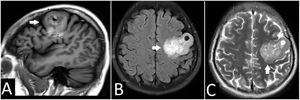

Resonancia magnética cerebral. A) Corte sagital, en secuencia en T1, con una gran masa frontal izquierda (flechas blancas). B) En la secuencia T2 – TIRM se observa hiperintensidad heterogénea con quiste intratumoral. C) En la secuencia T2 – TSE se observa la afectación de la corteza y sustancia blanca.